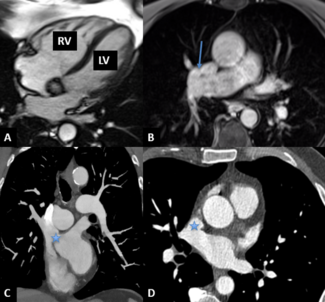

A 73-year-old man with a history of hypertension, hyperlipidemia, and obesity presented for cardiovascular evaluation. He was experiencing mild fatigue and dyspnea on exertion. Transthoracic echocardiogram showed right ventricular dilation,...